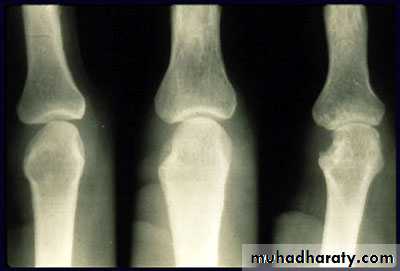

In chronic inflammatory polyarthritis, marginal joint erosions are seen earliest in the small joints of the hands, wrists, and feet in patients with RA.

Chronic gout can also cause erosions with an overhanging edge that typically involve small peripheral joints such as the first MTP joint.